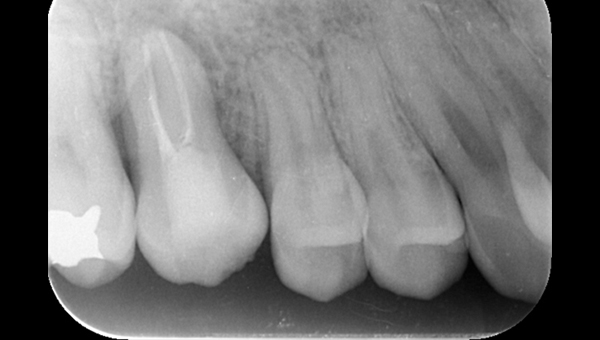

2021.4.3 定期検診時

この時はまだ症状がなかった

しかし歯は縦に割れており、いつ痛みが出てもおかしくないような状態であることは説明していた。